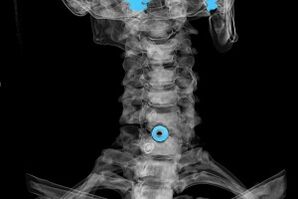

Diagnosis is established on the basis of characteristic symptoms, as well as using:

- X-rays. This method is ineffective, especially in the late stages of the development of osteoarthritis.

- MRI (magnetic resonance imaging) of the cervical spine.A method that allows you to see the bone structure, herniated discs, their size and direction of growth.

- Computed tomography.A less effective solution than MRI, as it is difficult to determine the presence and size of the hernia.